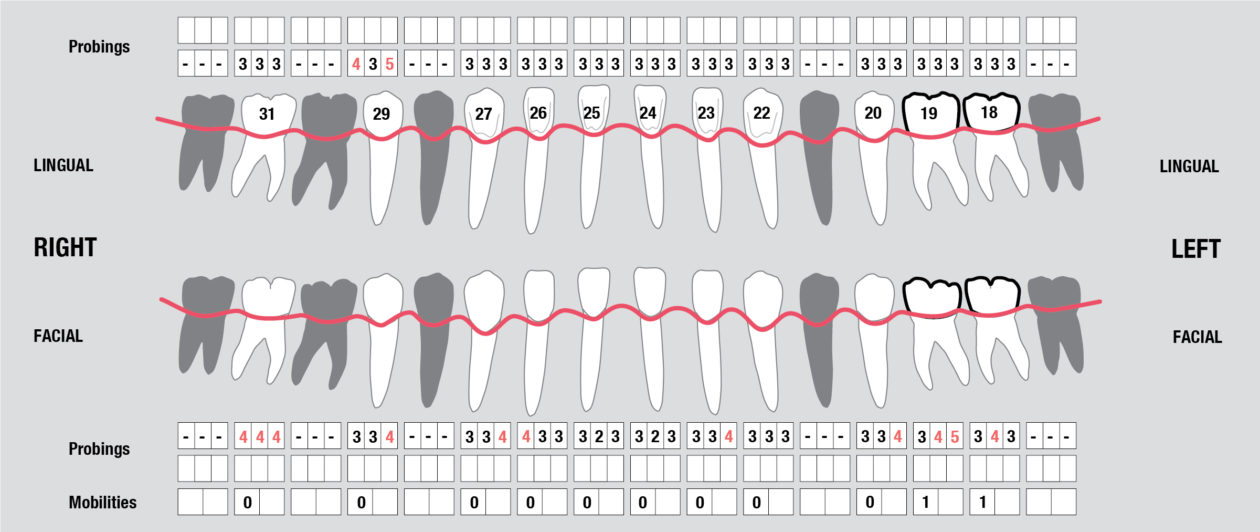

Tooth no. 19 was isolated with a dental dam under local anesthesia. All existing restorative material and decay was excavated leaving a very evident crack into the pulp, down to the pulpal floor. The mesial canals were completely calcified, the decay extended beyond the bone level. This tooth was diagnosed as hopeless and scheduled for removal. A provisional was placed at this appointment.

Tooth no. 30 was deemed hopeless at initial evaluation and extracted.

Full Mouth Radiographic Series, Maxillary and Mandibular Intraoral Scans, Digital Jaw Relation Recording with a Leaf Gauge, Complete Photographic Series, Periodontal Charting, Restorative Charting.